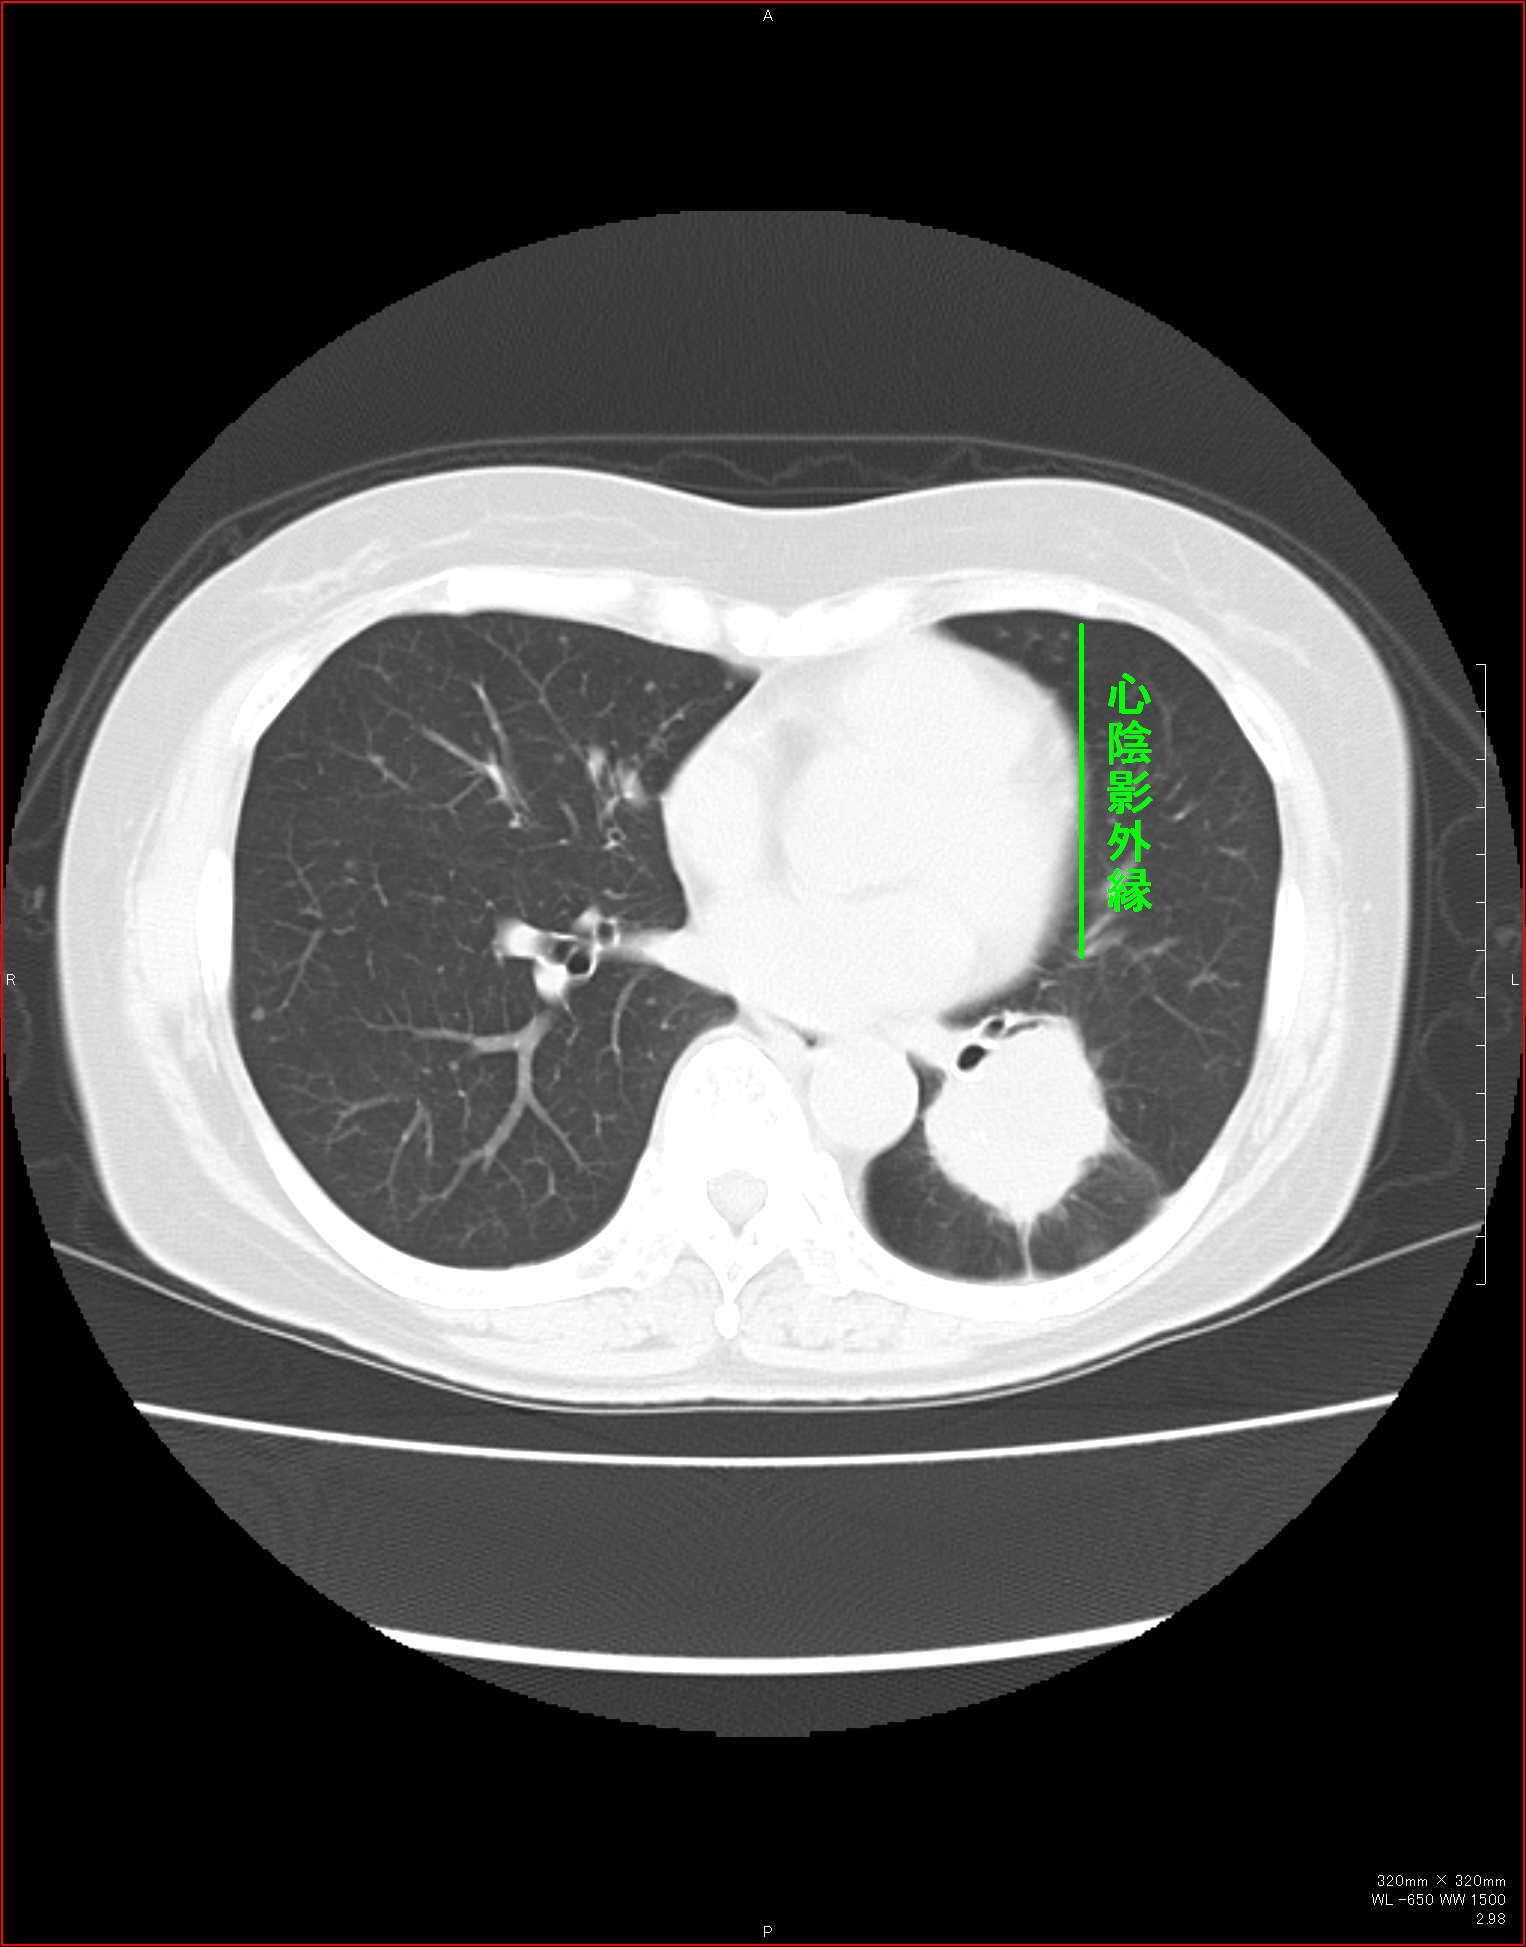

CTで見ると…

3Dだと、こうなります。

気管狭窄ですね。こういう所見もレントゲンで捉えることができるのです。